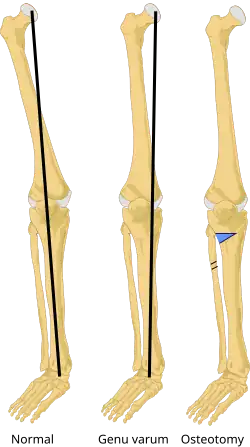

Knee osteotomy is commonly used to realign arthritic damage on one side of the knee. The goal is to shift the patient's body weight off the damaged area to the other side of the knee, where the cartilage is still healthy. Surgeons remove a wedge of the tibia from underneath the healthy side of the knee, which allows the tibia and femur to bend away from the damaged cartilage.[7]

During a high tibial osteotomy, surgeons remove a wedge of bone from the outside of the knee, which causes the leg to bend slightly inward. This resembles the realigning of a bowlegged knee to a knock-kneed position. The patient's weight is transferred to the outside (lateral) portion of the knee, where the cartilage is still healthy.[10]